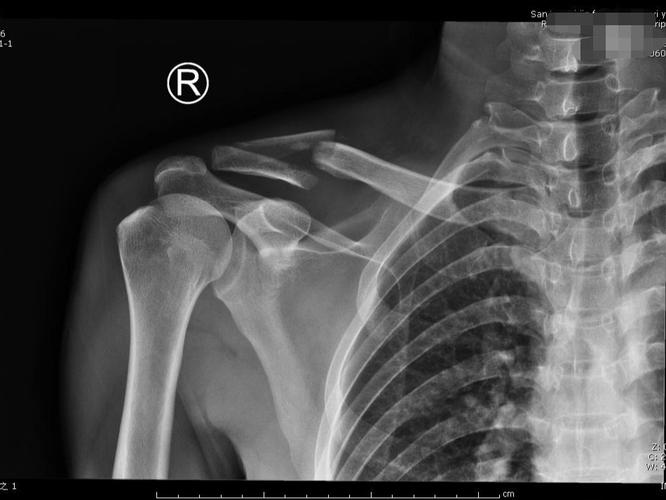

锁骨骨折微创治疗之mipo

锁骨骨折

锁骨青枝骨折